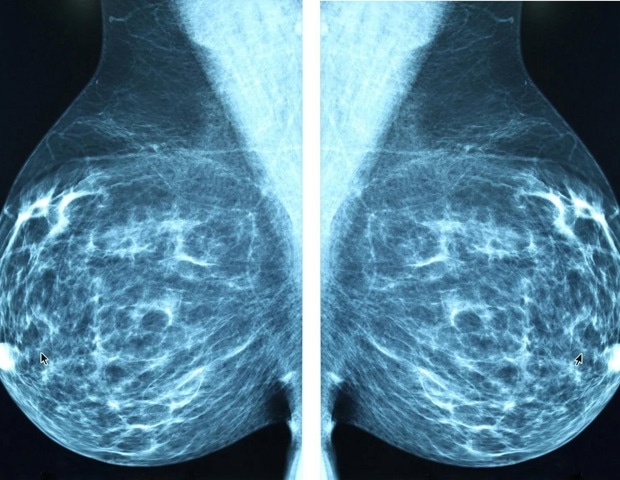

Triple-negative breast cancer (TNBC) represents the most aggressive subtype of breast cancer and significantly impacts African American women, who face a higher incidence of this disease. A pivotal study spearheaded by researchers at Roswell Park Comprehensive Cancer Center addresses this important issue by exploring the genetic factors relevant to TNBC in this demographic. The lead author, Dr. Song Yao, MD, PhD, along with a team of collaborators, published their findings in the esteemed journal Nature Genetics.

Through comprehensive whole-exome and RNA sequencing, the researchers established an extensive mutational profile derived from 462 African American women diagnosed with TNBC. The analysis revealed that the mutational landscape in this group closely aligns with that found in Asian American and non-Hispanic white women. Notably, the study found no significant correlation between African ancestry and the specific genetic mutations observed.